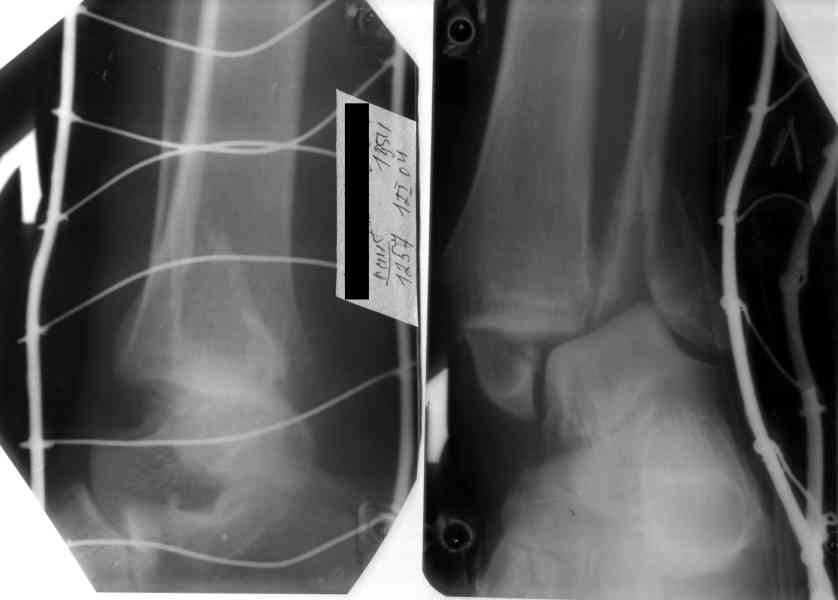

Здесь финальный снимок 73 летней с

сопутствующей шизофренией, латерально бридж

пластину (соединили дистальный конец с диафизом не трогая место перелома) и медиально перкутанно

двумя шурупами. В этам случае без гипса не

обойтись.